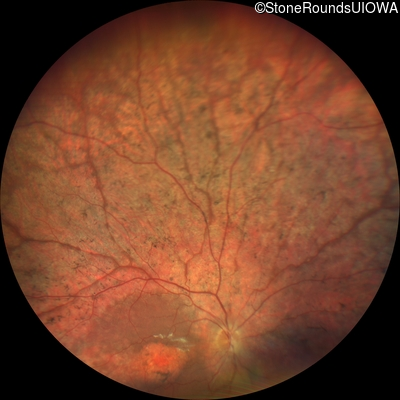

Fundus Photography - Right - 20/160

Exemplar

Fundus Photography - Left - 20/80 -1